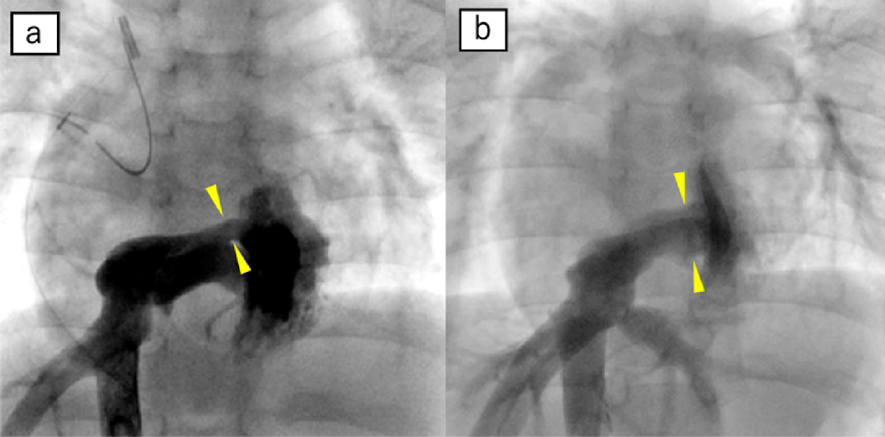

入院後経過(Fig. 1)

99mTc消化管シンチグラフィーで回盲部に異常集積を認めPLEと診断した.また胸水は非乳糜であり,低アルブミン血症に続発したと考えられた.心臓カテーテル検査では下大静脈(inferior vena cava: IVC)baffle内に最小径3.6 mmの狭窄を認め,6 mmHgの圧較差を伴い,IVC圧は10 mmHgと上昇していた(Fig. 2).また,上大静脈(superior vena cava: SVC)圧と肺動脈圧はともに10 mmHgであり,Glenn吻合部に狭窄は認めなかった.アルブミン補充,利尿剤,プレドニゾロンを併用し,入院9日目に胸水は消失し,Alb値も3.5 mg/dLに上昇を認めたため入院17日目に退院した.その後PLE再燃やステロイド薬長期使用の副作用を懸念し,PLE発症2か月後に外科的にIVC baffle狭窄解除を施行した.術中所見ではbaffle内の冠静脈洞unroofing部位に肥厚組織を認め,これを切除し狭窄を解除した(Fig. 3).術後2か月でプレドニゾロンを終了し,術後1年の心臓カテーテル検査で狭窄解除部前後に圧較差を認めずIVC圧が4 mmHgに改善したことを確認した.その後5年の観察期間で再燃なく経過した.

Pediatric Cardiology and Cardiac Surgery 39(1): 9-15 (2023)

Fig. 2 Inferior vena cava angiograms

(a) Preoperatively a stenosis is demonstrated in the inferior caval pathway. (b) Postoperatively there is significant improvement in the stenosis.